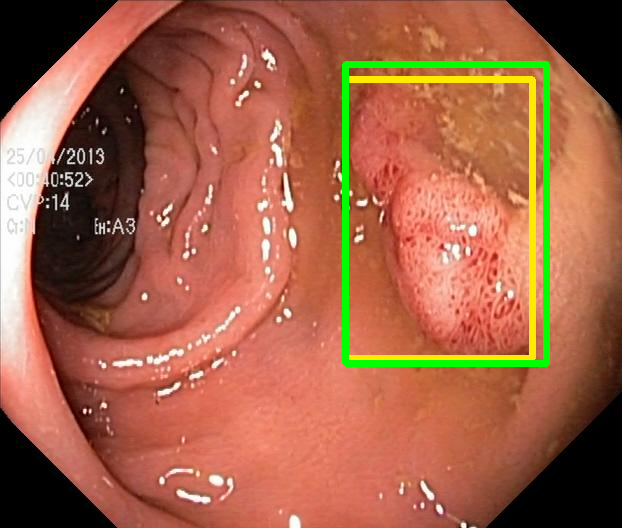

We evaluate the resulting object detection models using the test data, which is pre-processed in the same manner as the validation data, with AP@[.5:.95] (AP for conciseness), AP@.5 (AP50), and AP@.75 (AP75) computed for predicted bounded boxes with a confidence score \geq0.05. For all metrics, a higher value indicates better performance. The results are presented in Table VI, and some examples for predicted bounding boxes with a confidence score \geq0.5 are shown in Fig. 1.

Figure 1: Targets (yellow bounding boxes) and predictions (green bounding boxes) for two randomly selected instances of the Kvasir-SEG test set. For conciseness, we denote ResNet50s with RN, ViT-Bs with VT, Hyperkvasir-unlabelled with HK, ImageNet-1k with IN, MoCo v3 with MC, Barlow Twins with BT, MAE with MA, supervised pretraining with SL, and no pretraining with NA-NA.